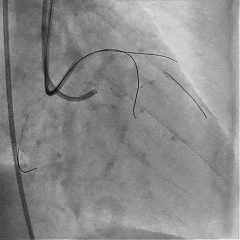

双侧造影,观察闭塞起始位置、长度、走行等

尝试通过RCA-圆锥支侧枝逆向开通LAD :

微导管辅助下,用SUOH03导丝尝试送入侧枝

经微导管TIP injection可见侧枝重度迂曲

侧枝重度迂曲,反复尝试未能通过